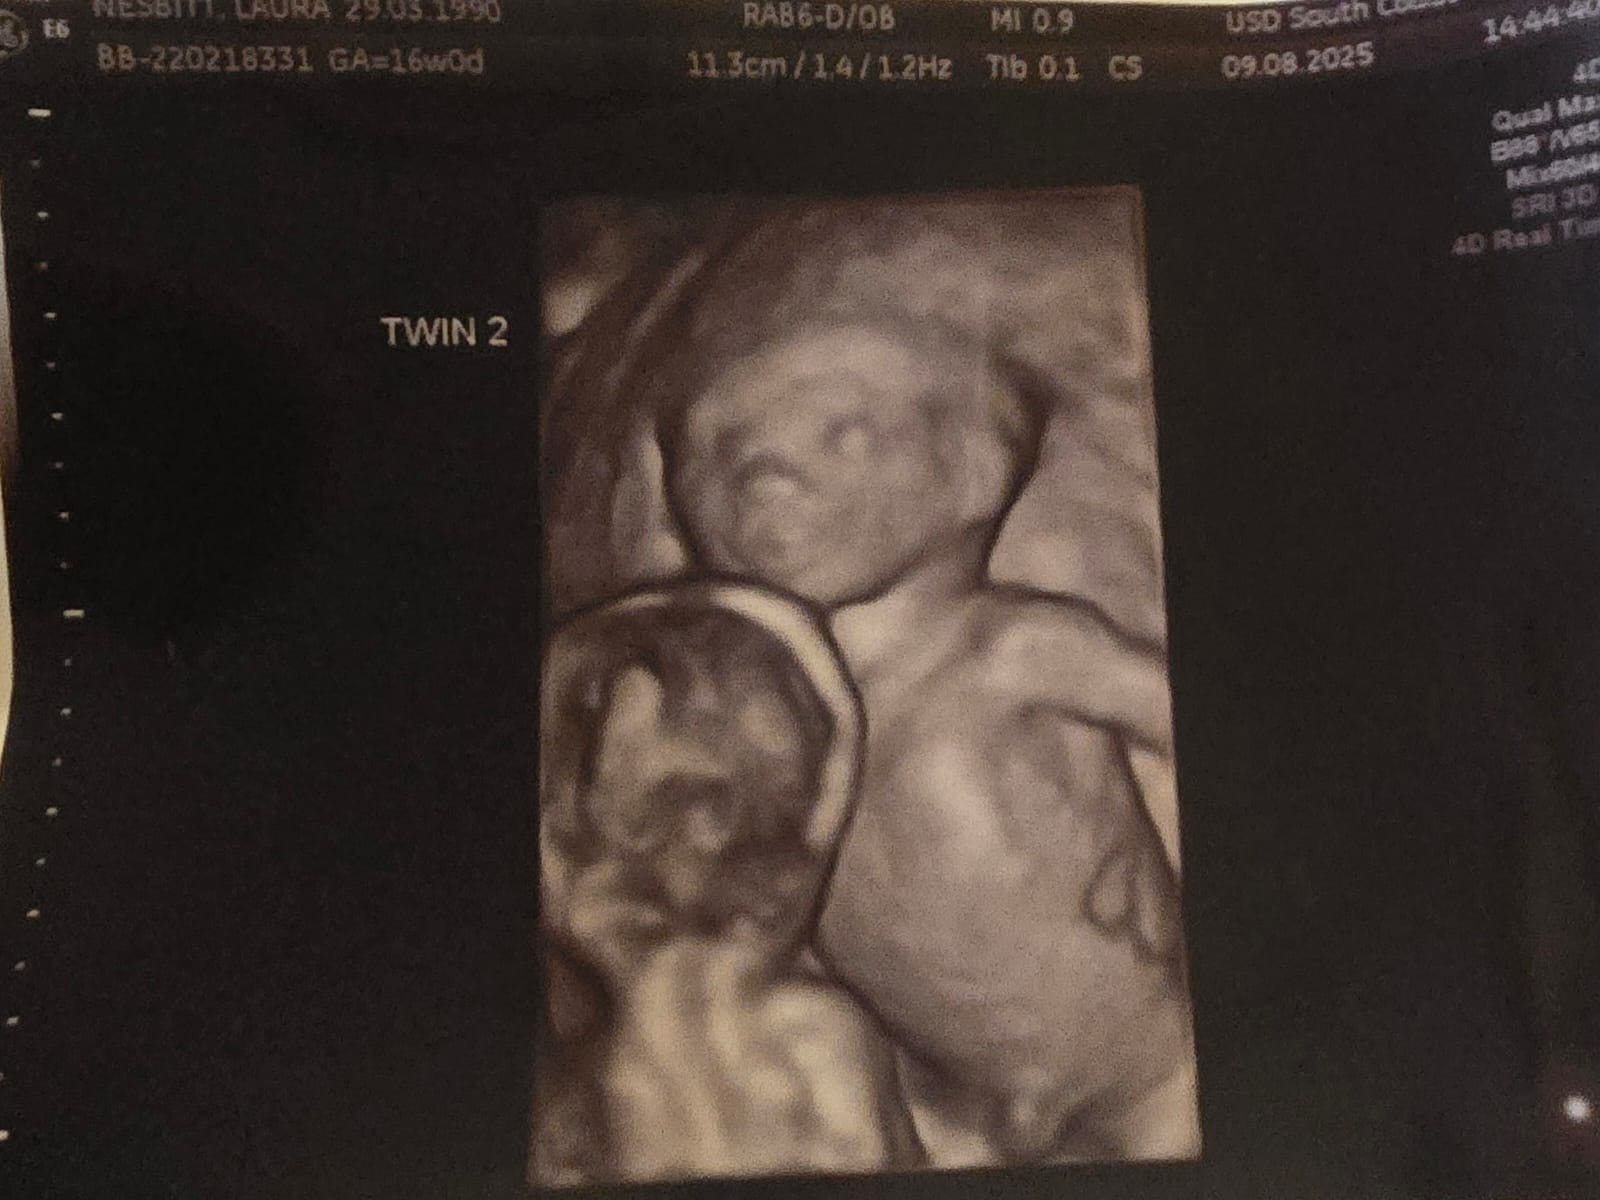

So we went to our 12week scan to surprisingly find out we are having identical twins. This was a big shock! But very happy to find this out. We then went to our 16weeek scan to find out that 1 baby is behind by 1 week compared to the other this is called TTTS with twin 1 being smaller and not getting enough fluid then twin 2 this is called - TWIN TO TWIN TRANSFUSION SYNDROME. We now have been refered to St George's twin specialist hospital in London to monitor and to have laser treatment to make sure they give both twins a good fighting start and to give the other twin that's developing behind more blood flow and nutrients.